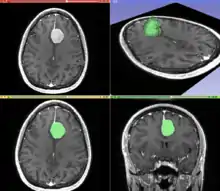

A T1 weighted MR image of the brain of a patient with a meningioma after injection of an MRI contrast agent (top left), and the same image with the result of an interactive segmentation overlaid in green (3D model of the segmentation on the top right, axial and coronal views at the bottom).

Segmentation is the process of partitioning an image into different meaningful segments. In medical imaging, these segments often correspond to different tissue classes, organs, pathologies, or other biologically relevant structures.[2] Medical image segmentation is made difficult by low contrast, noise, and other imaging ambiguities. Although there are many computer vision techniques for image segmentation, some have been adapted specifically for medical image computing. Below is a sampling of techniques within this field; the implementation relies on the expertise that clinicians can provide.